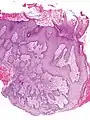

![]() Microscopic image of the epidermis, which constitutes the outer layer of skin, shown here by the white bar | |

![]() Microscopic image showing the layers of the epidermis. The stratum corneum appears more compact in this image than above because of different sample preparation. | |

Pseudoepitheliomatous hyperplasia (PEH), low magnification, with acanthotic squamous epithelium with irregular thick finger-like downgrowths into the underlying dermis.